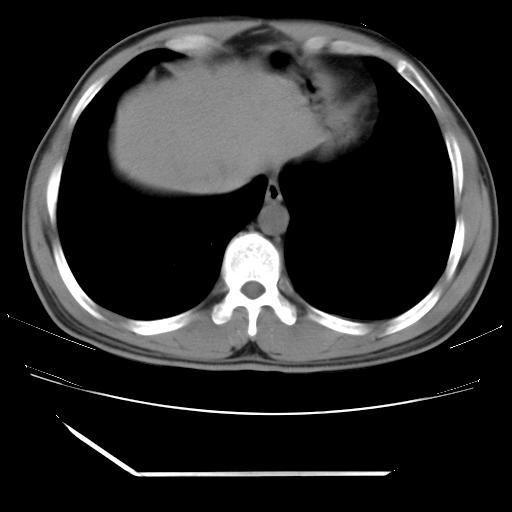

男,38岁,于2009年8月9日晚突发左侧胸痛,今x线提示左下肺阴影,为了明显确诊断,行ct检查,

血常规:嗜酸性细胞增高,单核细胞增高。

纵膈窗

病灶发生在下叶,密度均匀,边缘模糊、毛糙,周围血管纹理增强扭曲改变,靠近胸膜处病灶胸膜反应明显。

支持考虑---球形肺炎。

左肺舌叶病变。主体病灶呈类圆形中心密度低,成液化趋势周边班片影分布

考虑肺脓肿

虽然实验室检查支持炎性病变,且病变内有坏死改变(中央呈大片状低密度影),但仍不能掉以轻心,鳞癌也可以有这种影像改变。